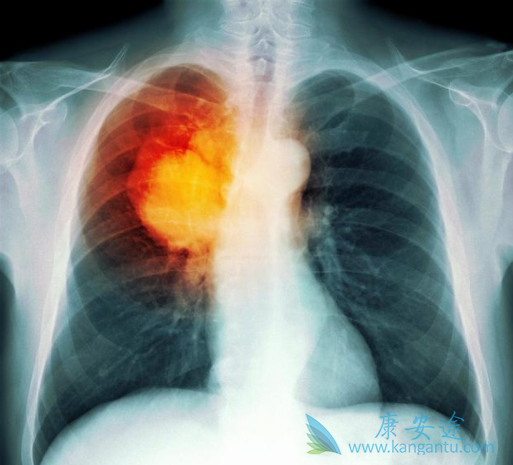

肺癌是日常生活中常见的一种癌症,而化疗是治疗肺癌的一种常用手段,那么患者什么情况下需要肺癌化疗?化疗时有哪些注意事项呢?下边小编就为大家介绍下与肺癌化疗相关的问题。肺癌化疗是化学药物治疗肺癌的简称,是利用化学药物组织癌细胞增殖、浸润、转移,直至最终杀死癌细胞的一种治疗方式。